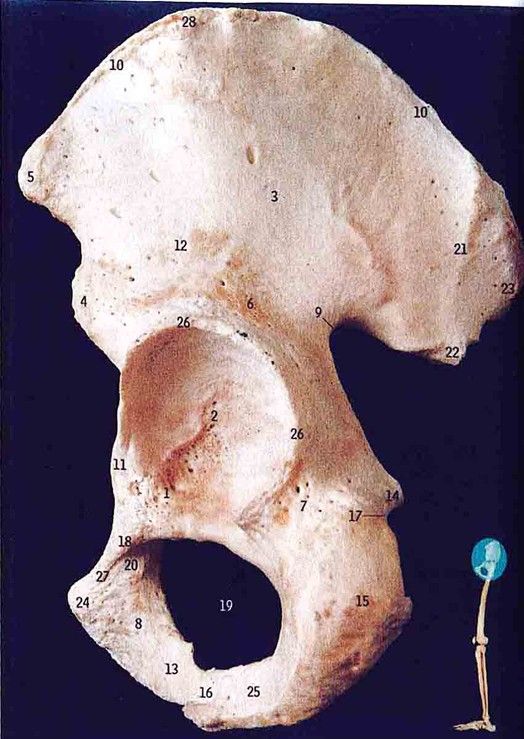

• Iliacus

• Psoas major

• Rectus femoris

All muscle inserted in lesser trochanter of femur

Nerve passing medial to Lesser trochanter?

Lateral cutaneous nerve of thigh (lateral femoral cutaneous nerve) (L2, 3)

Condition caused by its compression

Meralgia paresthetica

Muscles attached to ASIS?

Sartorius (origin)

Tensor fasciae latae (origin)Identify pubic tubercle

Number 24

Origin and insertion of gluteus medius

Origin: Ilium between posterior and anterior

Insertion

Greater trochanter of femur

gluteal linesWhat is its function during walking?

Support the body when walking

Prevent the pelvis from drooping to the opposite sideWhat are the main flexors of the hip?

Iliacus

Psoas major (main one)

Rectus FemorisWhere is it inserted?

Lesser trochanter of femur